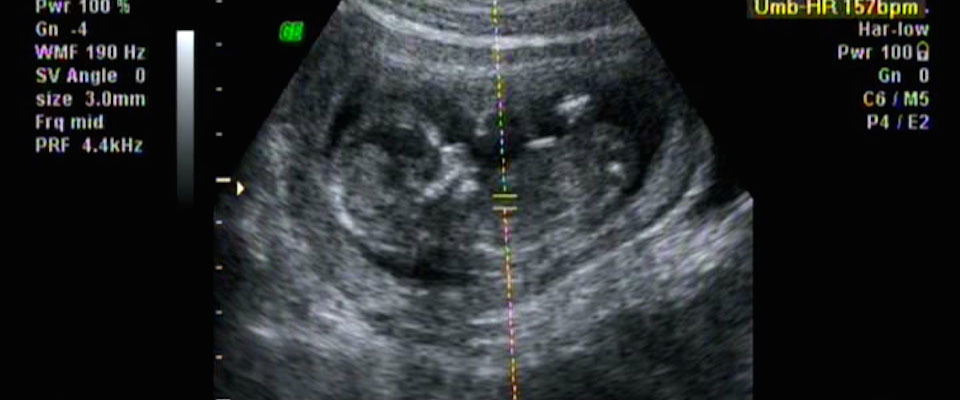

It is true that the evidence of our senses—“seeing the image of a recognizable human infant”—evokes a kind of “sympathetic identification” with the unborn baby in the womb. But moral conclusions depend on a kind of reasoning, not merely on “sensibilities” upon which we do not reflect. So that ultrasound image reveals the presence of a human child in utero. What was it before it was visibly recognizable as a child? The answer is obvious. It was a child then too, with all the attributes of a human child appropriate to its stage of development. And before that, the same. And before that, the same . . . all the way back to the moment of conception, when it came to be what it is.